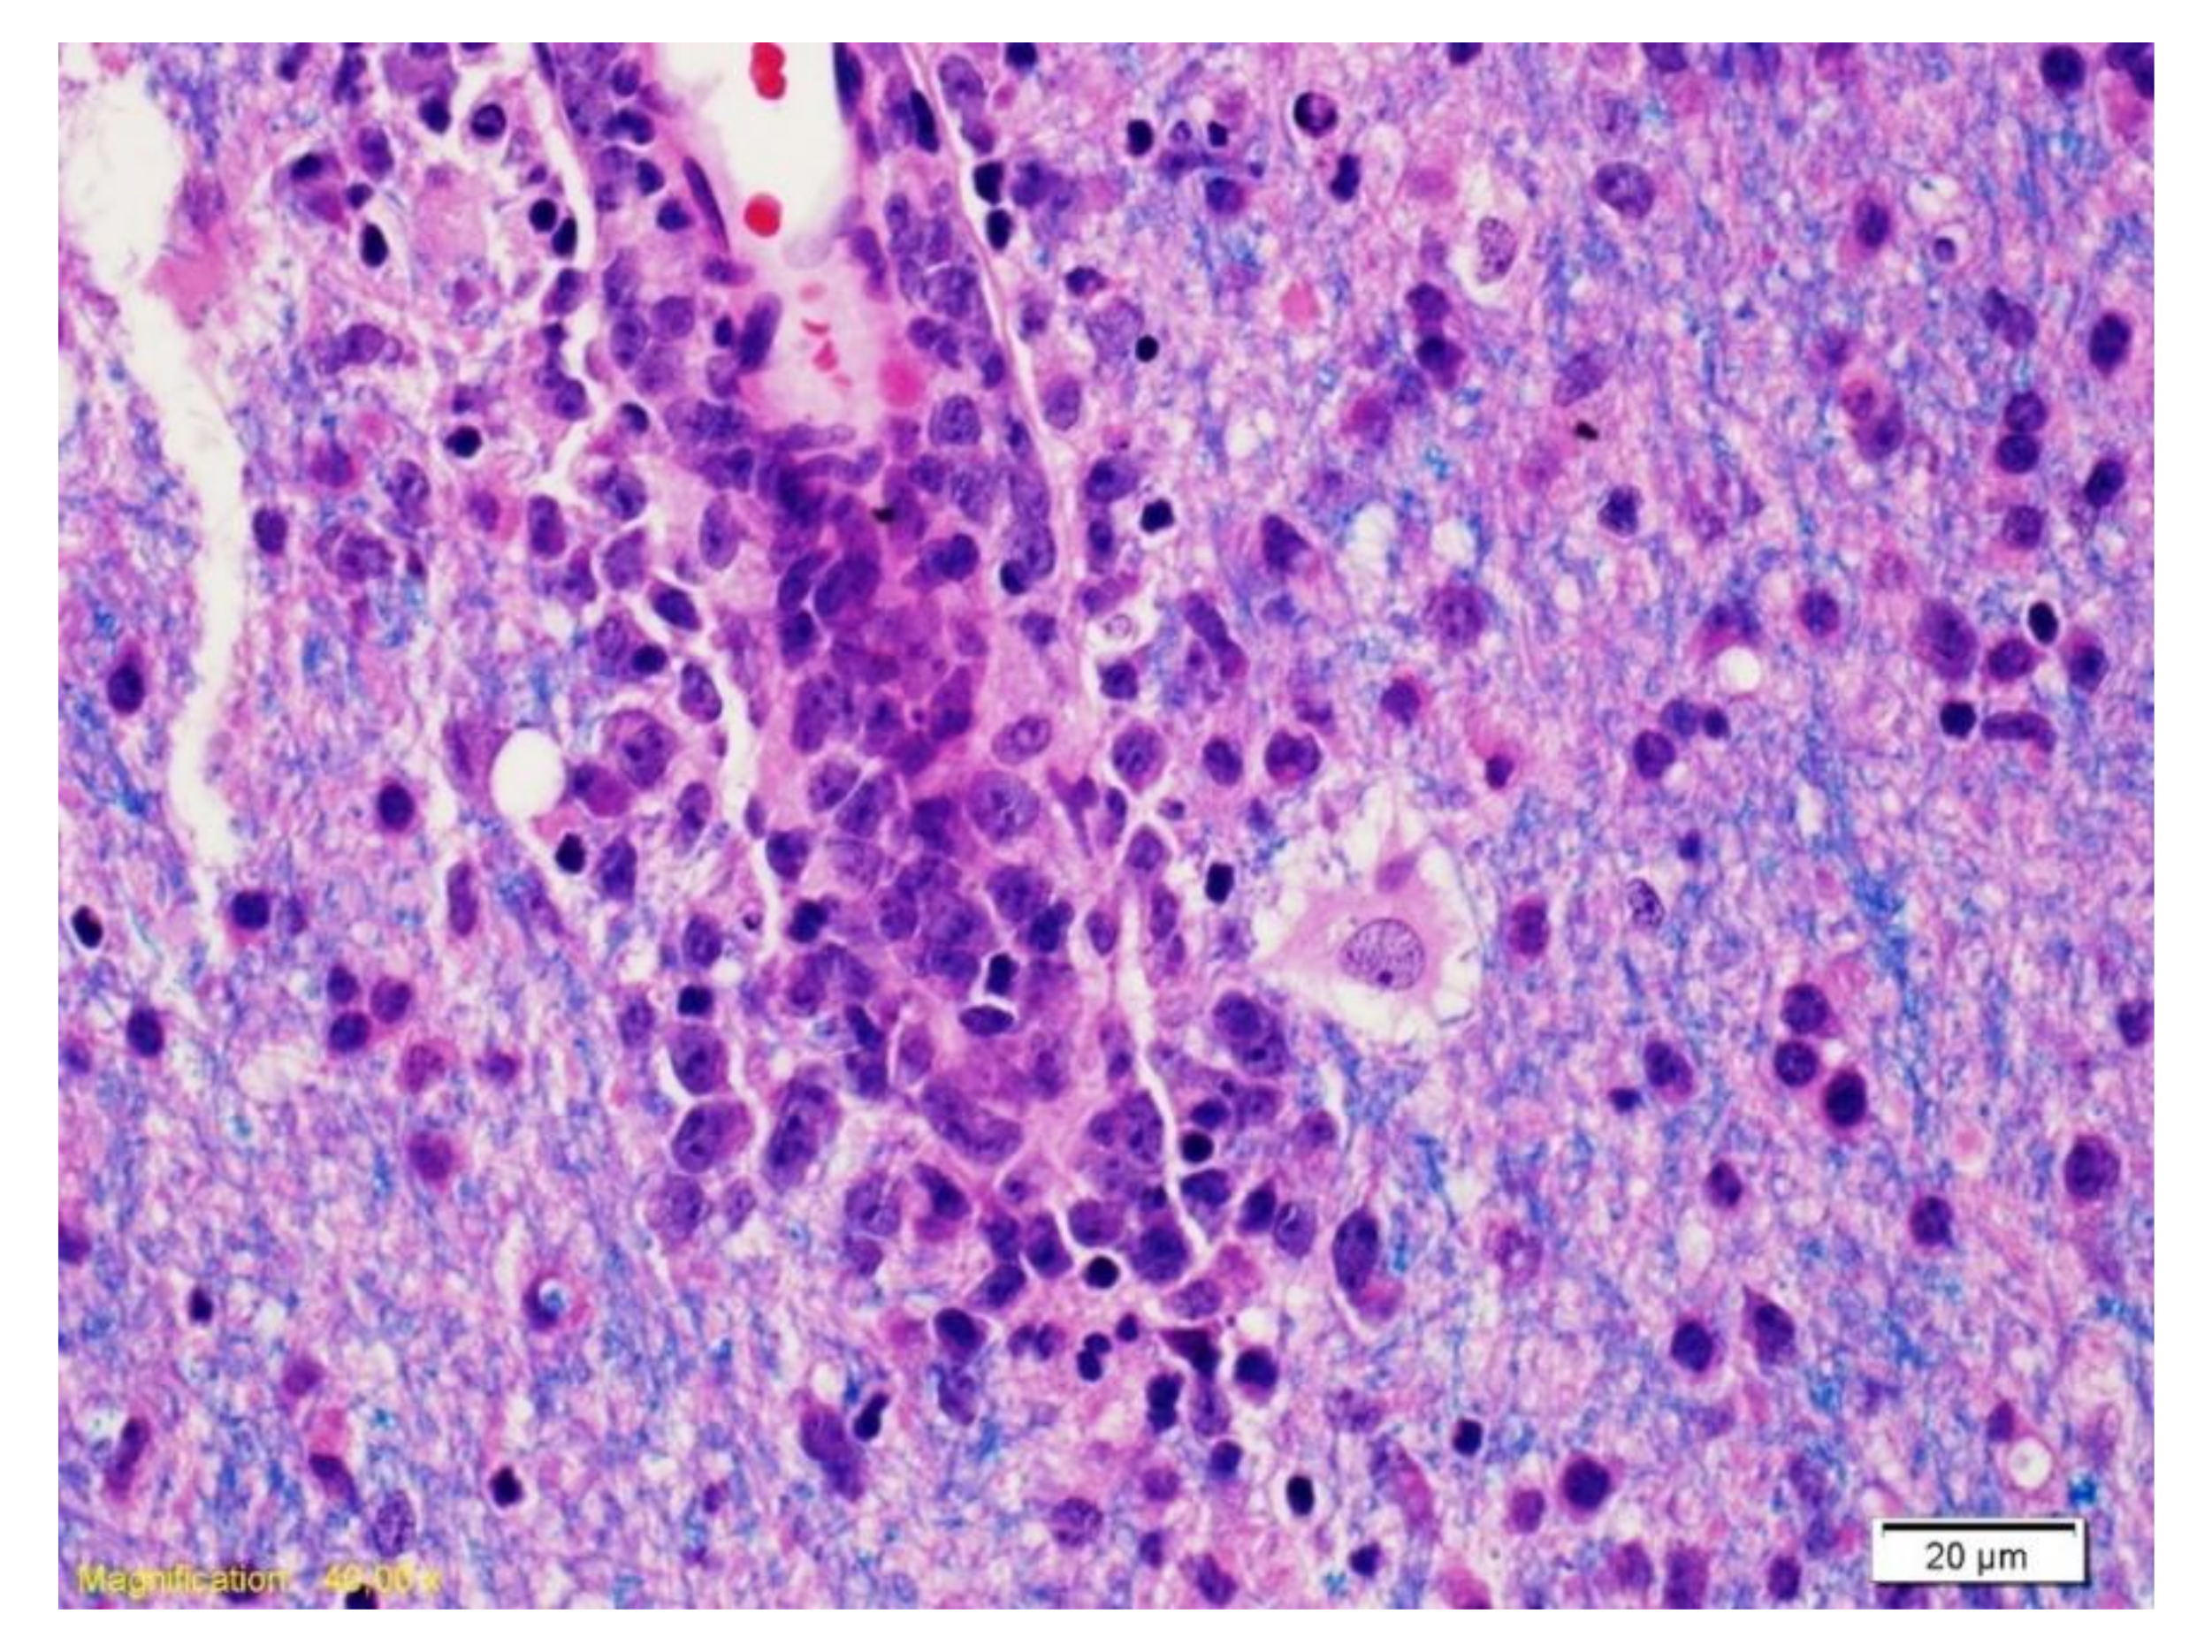

Figure 3.

The Luxol Fast Blue coloration combined with hematoxylin/eosin (LFB/H&E) highlights a vessel surrounded by cells with large nucleolus nuclei corresponding to neoplastic B lymphocytes and myelin (blue).